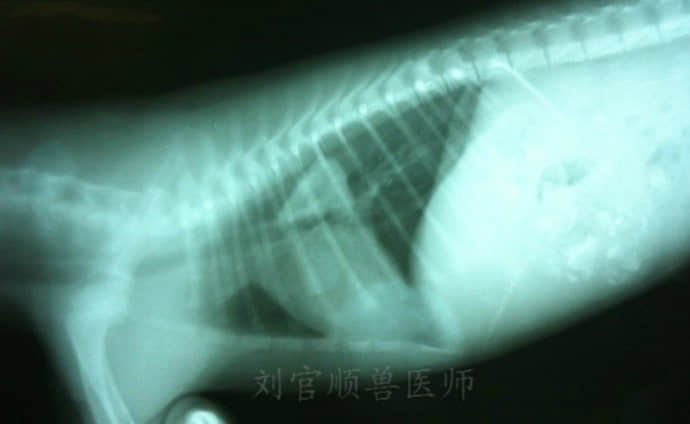

X-线检查:心基部食道有一三角形高密度异物,胃内不规则异物(如下图)

诊断:食道异物,胃内异物